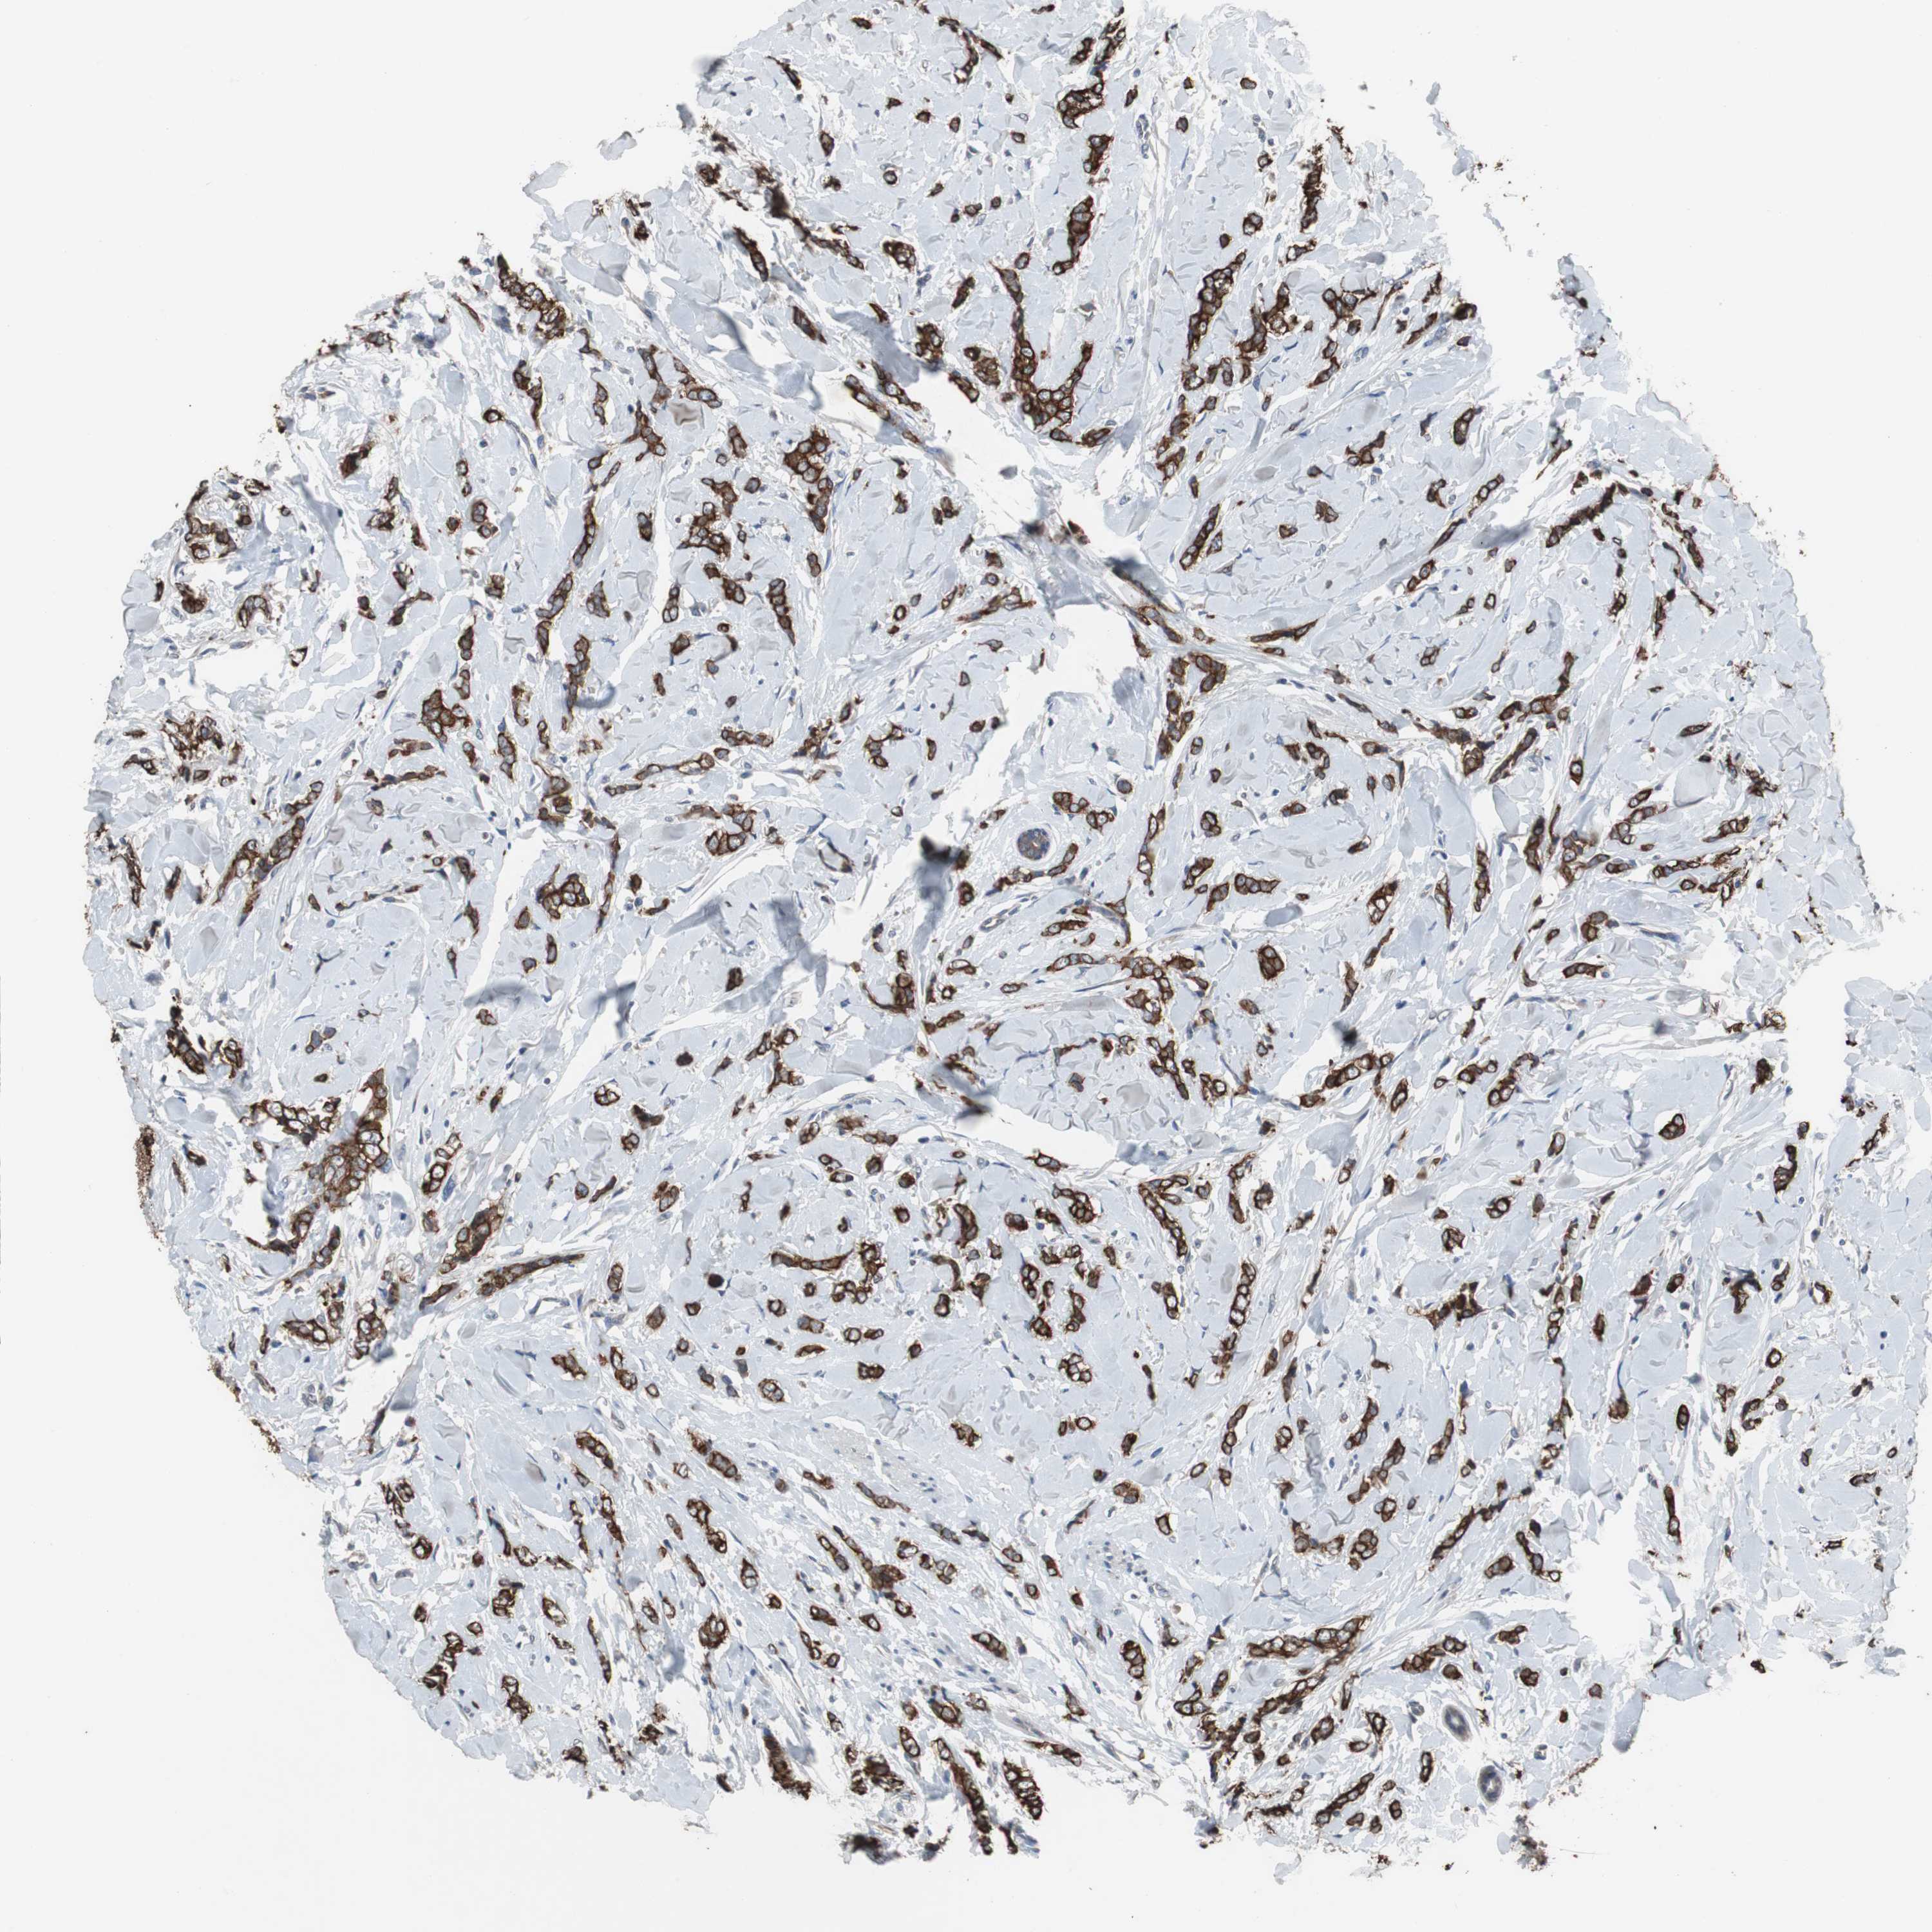

CANCER BREAST CANCER Show tissue menu

BRCA TCGA BRCA VALIDATION PROTEIN EXPRESSION